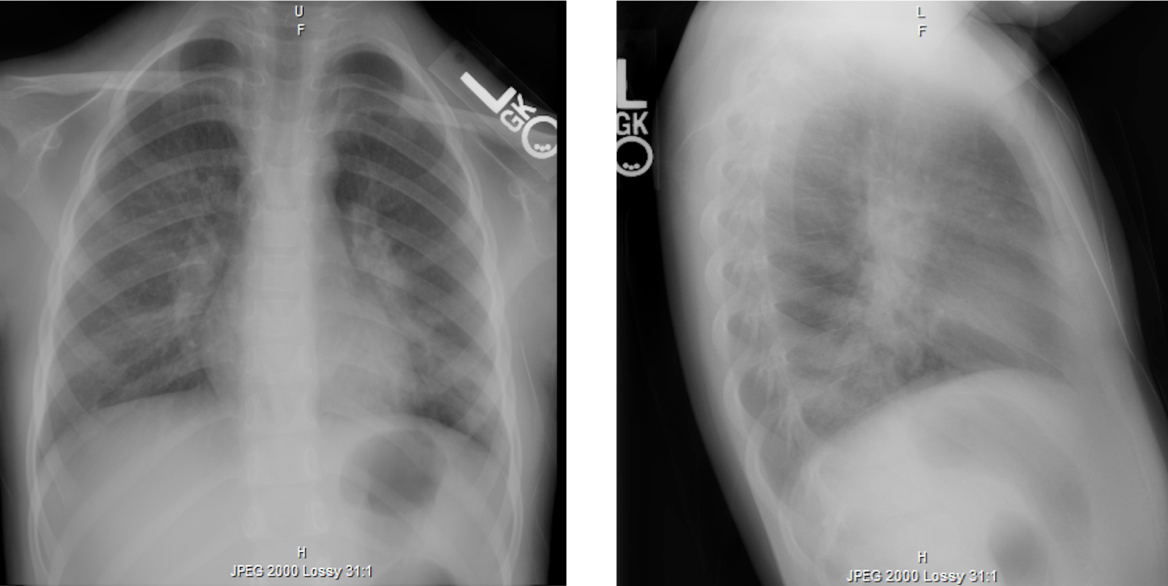

A 4-year-old girl with a history of 3 prior episodes of lobar pneumonia presented with a 2-day history of fever, with a temperature as high as 39°C. Eight days prior, the child had been referred for admission by her pediatrician for fever, leukocytosis (28,000 white blood cells/µL), and a left-sided infiltrate on chest radiographs (Figure 1). She had received 3 days of inpatient therapy with intravenous clindamycin to ensure lasting defervescence, waning leukocytosis, and falling levels of inflammatory markers; no oxygen requirement was noted throughout the hospitalization.

Figure 1. Chest radiographs demonstrating left lower-lobe opacity consistent with unilobar pneumonia.